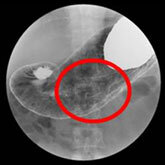

当院は循環器専門病院である一方、予防医学センターでは上部消化管造影検査も行っており、食道や胃に対してバリウムを用いた検査により、病気の早期発見が可能となっております。